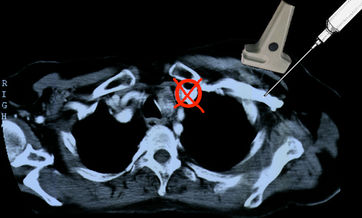

Punktion der Vena subclavia

Die infraclaviculäre Punktion der Vena subclavia anhand anatomischer Landmarken wurde im zweiten Weltkrieg entwickelt. ( R Aubaniac: L’ injection intraveineuse sous-claviculaire: avantages et technique. Presse Medicale 1952; 60:1456)

Kriegschirurgie ist sie auch geblieben. Bei dieser Methode wird in einer anatomisch heiklen Region, in der neben der Vene mehrere lebenswichtige Organe (Lunge, hirnversorgende Arterien, Ductus thoracicus, N. phrenicus, Plexus brachialis) dicht beieinander liegen, mit einer dicken Kanüle blind herumgestochert und dabei en masse Komplikationen erzeugt. Es ist nichts dagegen einzuwenden, wenn diese Methode auf dem Hauptverbandsplatz eines afrikanischen Kriegsschauplatzes in Ermangelung besserer Möglichkeiten noch praktiziert wird, unter elektiven Bedingungen in einer medizinischen Einrichtung eines zivilisierten Landes hat sie wegen der exorbitanten Rate leicht vermeidbarer Komplikationen ganz sicher nichts mehr zu suchen.

Um die Vena subclavia zu punktieren, muß horizontal unter der Clavicula in Richtung Manubrium sterni eingestochen werden. Dies gelingt nur, wenn der Patient auf einer harten Unterlage mit einem Hypomochlion unter der Wirbelsäule liegt, dass die Schultern nach hinten fallen.

Bei falscher Lagerung ohne Hypomochlion oder bei Punktion im Bett mit weicher Matratze führt die vorstehende Schulter zu schräger Punktion mit Verletzung der Lunge und Pneumothorax.

Bei älteren Patienten ist das Gewebe zwischen 1. Rippe und Clavicula oft sehr hart oder verknöchert. Wird dann zuviel Druck auf die Nadel ausgeübt, geht sie durch die Vene in die dahinter liegende A. carotis der Gegenseite mit der Folge eines Mediastinalhämatoms.

Argumente gegen Punktion der Vena subclavia

-Intimaläsionen durch Druck des Katheters und ständige Bewegung an der Kathetereintrittsstelle verursachen Stenosen und Thrombosen bei 60% rechts bis 90% links ( M DeCicco, M Matovic, L Balestreri, G Panarello, D Fantin, S Morassut, V Testa: Central venous thrombosis: an early and frequent complication in cancer patients bearing long-term silastic catheter. A prospective study. Thrombosis Res. 1997;96:101-113.)

Thrombosen der Vena subclavia sind symptomarm und werden deshalb fast immer übersehen. Sie sind aber nicht harmlos und oft die Ursache einer Lungenembolie (M.Monreal, A. Ravantos, R. Lerma, J Ruiz, E Lafoz, A Alastrue, JF Llamazares: Pulmonary embolism in patients with upper extremityDVT associated to venous central lines- a prospective study. Thromb Haemost 1994; 72: 548-550).

Bei diesem Patienten hat der Chirurg nicht nur auf die obligatorische Durchleuchtng verzichtet, sondern auch noch die ganzen 50 cm Plastikschlauch, die in der Packung sind, ungekürzt in den Patienten geschoben, obwohl der Abstand von der Punktionsstelle bis zur Cava/Vorhofgrenze, wo die Katheterspitze liegen soll, nur 10-12 cm beträgt. Dem Patienten wurden mehrere Zyklen Chemotherapie ins Hirn infundiert, bis die resultierende Sinusvenenthrombose zur Entdeckung der Fehllage führte.

- Frustrane Punktion mit notwendigem Wechsel der Punktionsstelle bei 5-35% der Katheteranlagen.

- Infektionsrate doppelt so hoch wie bei Punktion der proximalen Vena jugularis.

- Pneumothorax bei 5-15%.

- Arterienpunktion (A. carotis oder subclavia der Gegenseite) mit Mediastinalhämatom, Hämatothorax, Intimadisektion/Apoplex bei 10%.

- Pinch off Syndrom bei 2%. Dabei wird der Katheter zwischen 1. Rippe und Clavicula abgeschert. Es kommt zuerst zur Extravasation bei Injektionen, dann zur Katheterfragmentation mit Embolisation in rechten Vorhof, rechten Ventrikel oder die Lunge. Solange das Katheterfragment noch im Herzen liegt, kann es oft transfemoral mit einer Schlinge extrahiert werden. Aus der Pulmonalarterie kann es nur durch eine offene Operation mit HLM entfernt werden.